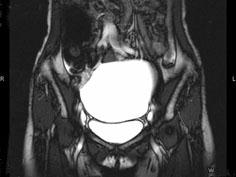

女, 62 岁, 左下腹持续性疼痛 3 天, 伴恶心、呕吐, 左侧附件区扪及一囊性包块, 活动, 表面光滑, 压痛明显,CT和MRI检查如图所示,下列说法...

问题 女, 62 岁, 左下腹持续性疼痛 3 天, 伴恶心、呕吐, 左侧附件区扪及一囊性包块, 活动, 表面光滑, 压痛明显,CT和MRI检查如图所示,下列说法错误的是 ( )

选项 A、结合临床症状,考虑为卵巢囊肿扭转 B、结合临床症状,考虑为卵巢囊腺瘤 C、该病灶包膜完整,边界清晰 D、膀胱向下压移位 E、左侧附件区一囊性占位性病变

答案 B